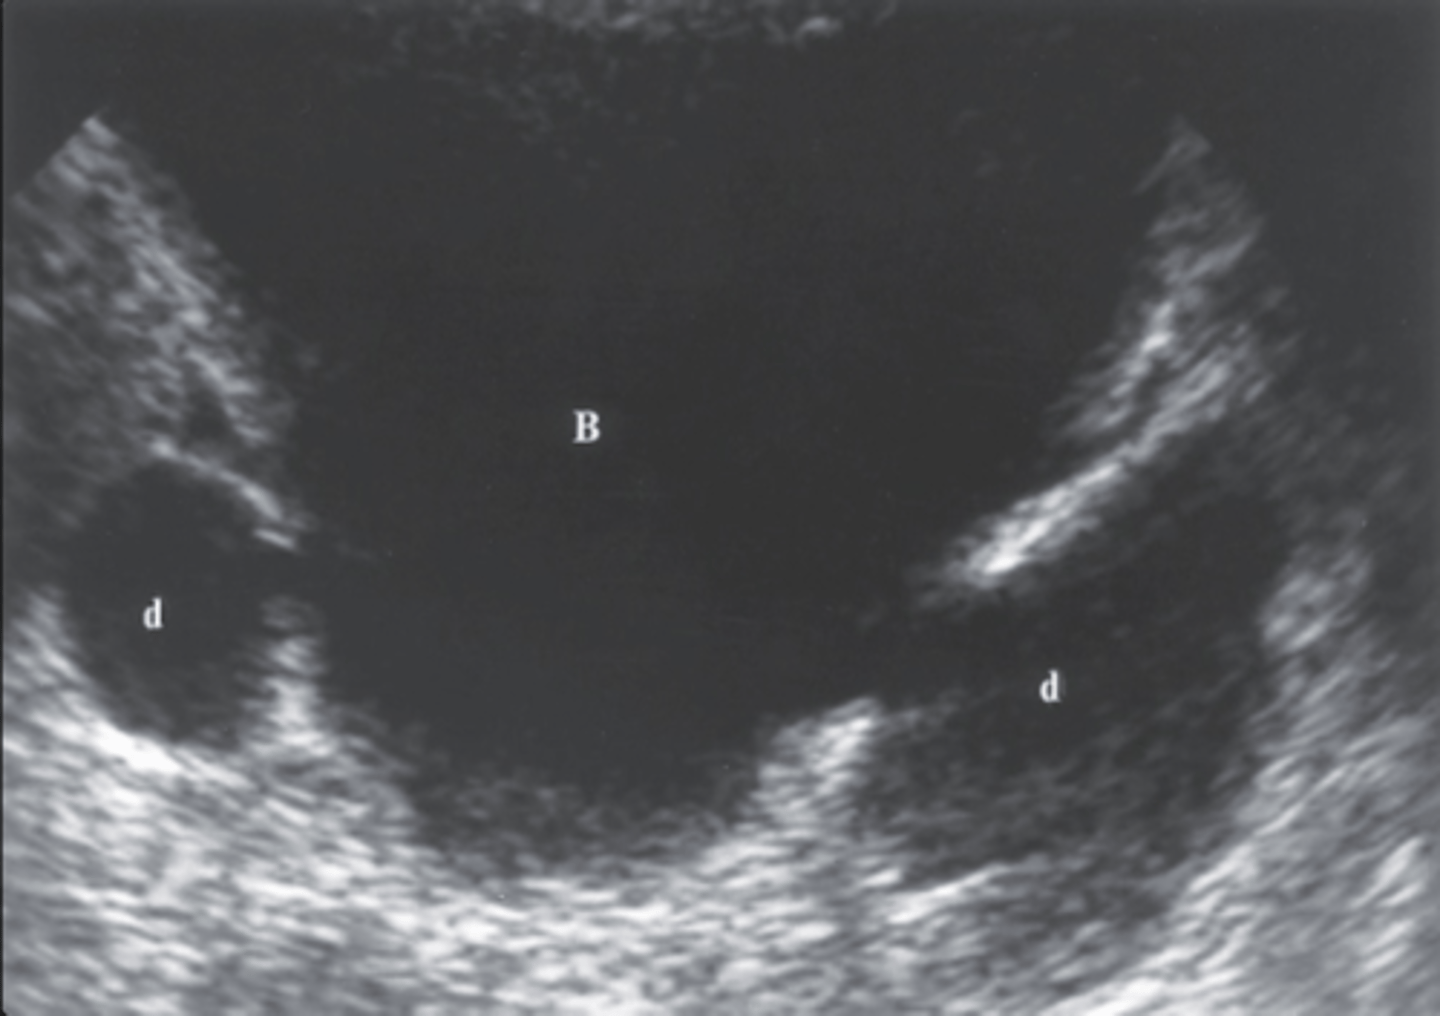

1. The sonographic finding in Figure 7-40 is most consistent with what diagnosis?

a. ARF

b. CRF

c. MCDK

d. ADPKD

2. What is the most common cause of the disorder noted in Figure 7-40?

a. Diabetes mellitus

b. Acute tubular necrosis

c. Smoking

d. Chronic pyonephrosis